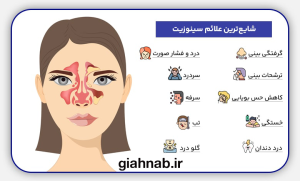

علائم سینوزیت

- گرفتگی و انسداد بینی

- ترشحات غلیظ و چرکی بینی

- سردرد و درد اطراف چشم و پیشانی

- تب و خستگی

- کاهش حس بویایی و چشایی

- سرفه بهویژه در شب